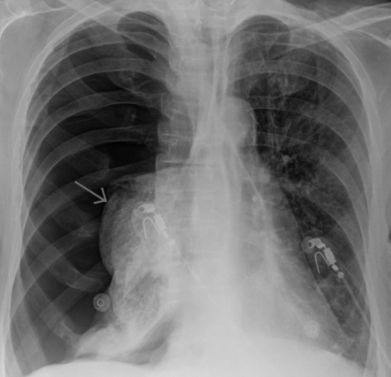

Пневмоторакс

Характер и локализация боли

Для пневмоторакса характерна острая боль в грудной клетке, которая усиливается при вдохе.

Иногда болевой синдром иррадиирует в плечо и спину со стороны пораженного органа.

Диагностика и лечение

Диагностика патологии состоит из:

- осмотра пациента;

- рентгенографии грудной клетки;

- компьютерной томографии;

- исследования газового состава крови;

- ЭКГ.